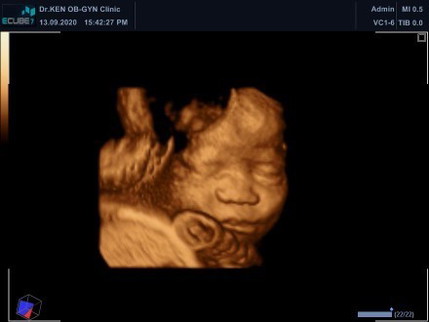

33+2week อยู่ในท่าขวางอยู่เลยจ้า

น้องยังไม่กลับหัวเลยค่ะปกติทารกจะกลับหัวตอนกี่สัปดาห์กันคะ #ขอบคุณสำหรับคำตอบค่ะ

เดี๋ยวก็กลับจ้าแม่ใจเย็นๆนะ ของเพื่อนเราอีกคนกลับหัวตอน 37 38 วีคเลย อีกคนกลับตอน 6 เดือนครึ่ง